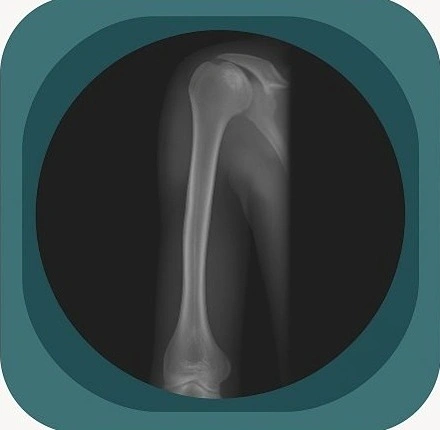

Explore high-quality X-ray anatomy from head to toe. Our database features carefully labelled images to visualize fine structures—perfect for radiologists, students, and surgeons.